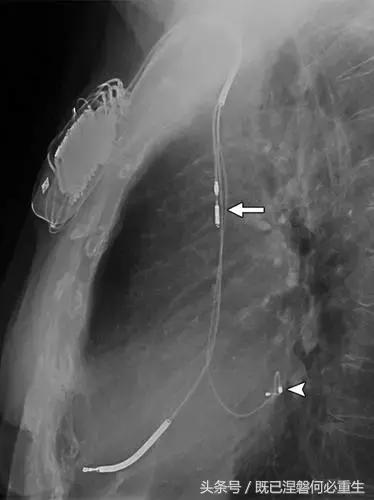

图。 7A 79岁的男性患有电极折断和迁移。

A,初始胸前X线片显示Pacesetter双腔起搏器低于锁骨的心房导线不完全断裂(变薄)(箭头)。

图。 7B 79岁的男性患有电极折断和迁移。

B,大约3年后,电极完全断裂,金属传导碎片(箭头)分离。 远端片段(箭头)已经偏移尾侧,但是由于围绕电极的射线可穿透鞘的约束效应而没有迁移到肺循环中。 引线和中心静脉导管最常见于锁骨和第一肋骨之间断裂,因为它们在臂运动期间被锁骨下肌肉或腱或肋锁韧带压缩[16]。

导致设备故障的最常见的X光检查原因之一是铅断裂。锁骨下静脉经过锁骨下的部位是骨折最常见的位置[16](图7A和7B)。在这个位置的损伤可能发生在导管或导线,并已被描述为锁骨下夹断综合征和锁骨下压溃综合征[16?18]。临床上,骨折的导线通常在患者中产生可以是连续的,间歇的或依赖于患者定位的症状。识别这些状况可能需要挑衅性的动作,例如等长臂锻炼,仰卧或侧向定位或Valsalva。设备检查将显示异常的起搏阻抗(如果绝缘破裂允许导体暴露则减小,如果导体断裂但绝缘完好则增加),感测错误和起搏捕获损失[12]。导线断裂或绝缘损坏可能导致感测或起搏异常。对心律失常的不适当的过感知或欠感应可能导致不适当的治疗,例如抗心动过速起搏和休克治疗,或不适当的抑制治疗。